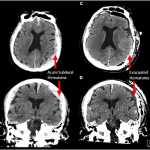

Η έκρηξη του Βεζούβιου το 79 μ.Χ μετέτρεψε τον εγκέφαλο ενός θύματος σε… γυαλί

Σε γυαλί μετατράπηκε ο εγκέφαλος ενός 25χρονου άνδρα που βρήκε τραγικό θάνατο στην πόλη Ηράκλειο (Ερκουλάνουμ) της Ιταλίας, κοντά στην Πομπηία, κατά την τρομερή...